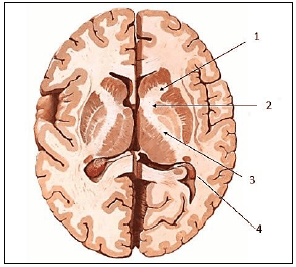

Cada hemisfério possui uma camada superficial de substância cinzenta, o córtex cerebral, que reveste um centro de substância branca – o centro medular do cérebro ou centro semioval. No interior dessa substância branca, há massas de substância cinzenta – os núcleos da base do cérebro. O centro branco medular do cérebro é formado por fibras mielínicas, que podem ser de dois tipos – de projeção ou de associação. As fibras de projeção se dispõem em dois feixes – o fórnix e a cápsula interna.

Assinale, a seguir, o número correspondente ao joelho da cápsula interna na imagem.